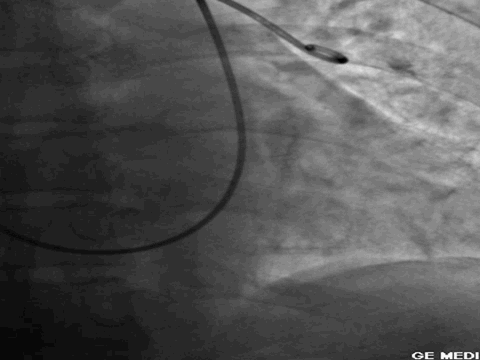

第一大名捕:肺动脉造影

红色箭头所指处即为栓子导致的充盈缺损。尽管肺动脉造影目前已经被肺动脉CTA所替代,但是其“老大”的地位还是无法撼动!

“老大”的绝招是其不仅可以提供整体的肺血管的解剖学资料,而且可以提供血流动力学参数,即可以用于诊断也可以用于治疗,如急性肺栓塞的导管内局部溶栓、捣栓、碎栓、抽栓,先天性肺动脉狭窄的球囊扩张、支架植入、肺动静脉瘘的栓塞治疗等。